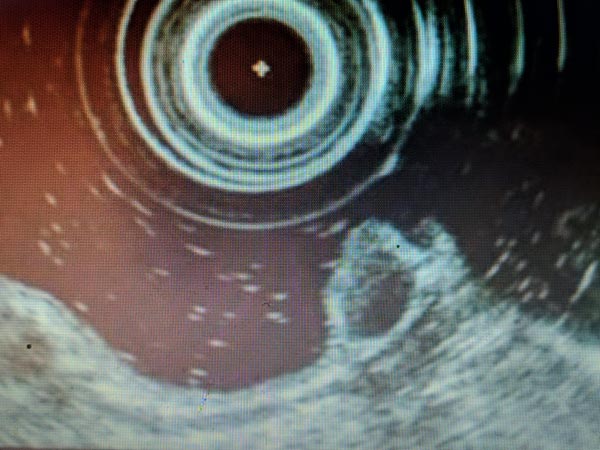

До проведения ESD выполняли эндоскопическую оценку образований в соответствии с Парижской классификацией, классификацией ямочного рисунка (Kudo S., 1996), сосудистого рисунка (Sano Y., 2010). Пациентам с подслизистыми образованиями выполняли эндосонографию прямой кишки и биопсию с иммуногистохимическим исследованием. В ходе эндосонографии выявлены гипоэхогенные образования размерами 0,6 и 0,8 см с интактным мышечным слоем и отсутствием увеличенных регионарных лимфатических узлов (рис. 1, 2).

Рис. 1. Подслизистое новообразование прямой кишки

Рис. 2. Эндосонограмма подслизистого новообразования прямой кишки